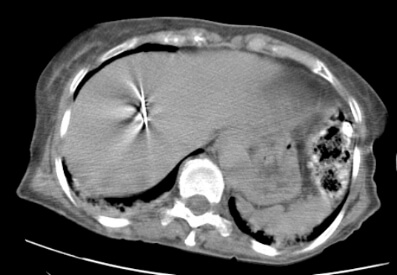

This is a CT image obtained during a microwave ablation case demonstrating the antenna within the target tumor.